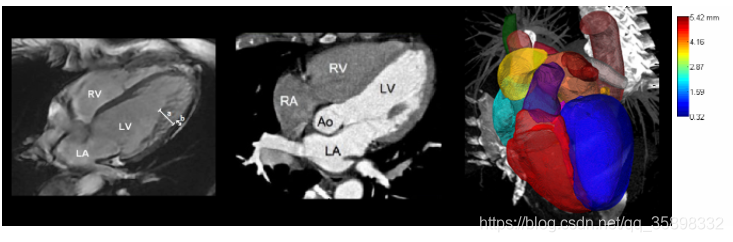

3、MMWHS CT/MRI heart

120 MRI/CT images,示意图如下: